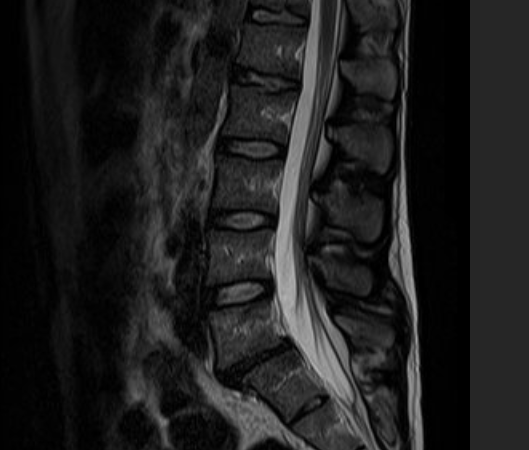

DIAGNOSI:

SPONDILOLISTESI LOMBARE DI II GRADO L5-S1

Risonanza magnetica pre-operatoria

Intervento chirurgico eseguito:

STABILIZZAZIONE PERCUTANEA SEMPLICE

Radiografia lombare post operatoria